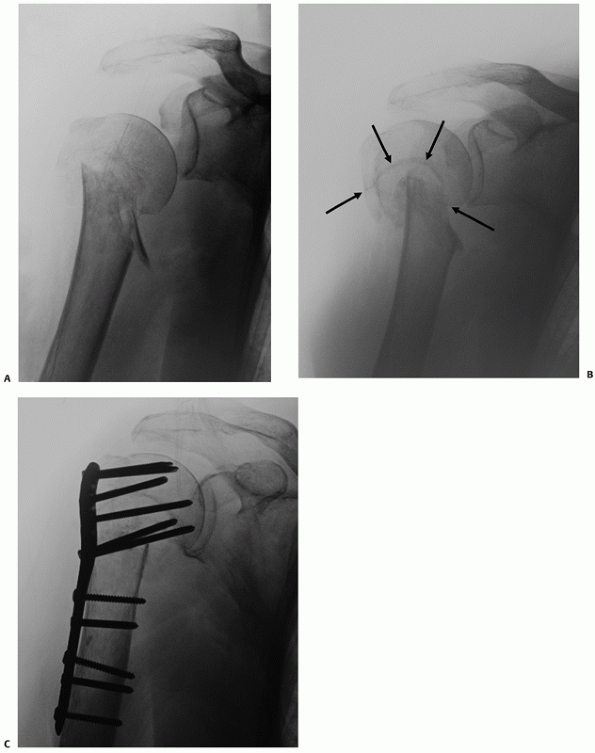

![]() |

FIGURE 35-10 Many seemingly isolated greater tuberosity fractures (A) actually have undisplaced anatomic neck fracture lines (arrow), which are only seen when a correctly orientated anteroposterior view is taken (B).

|